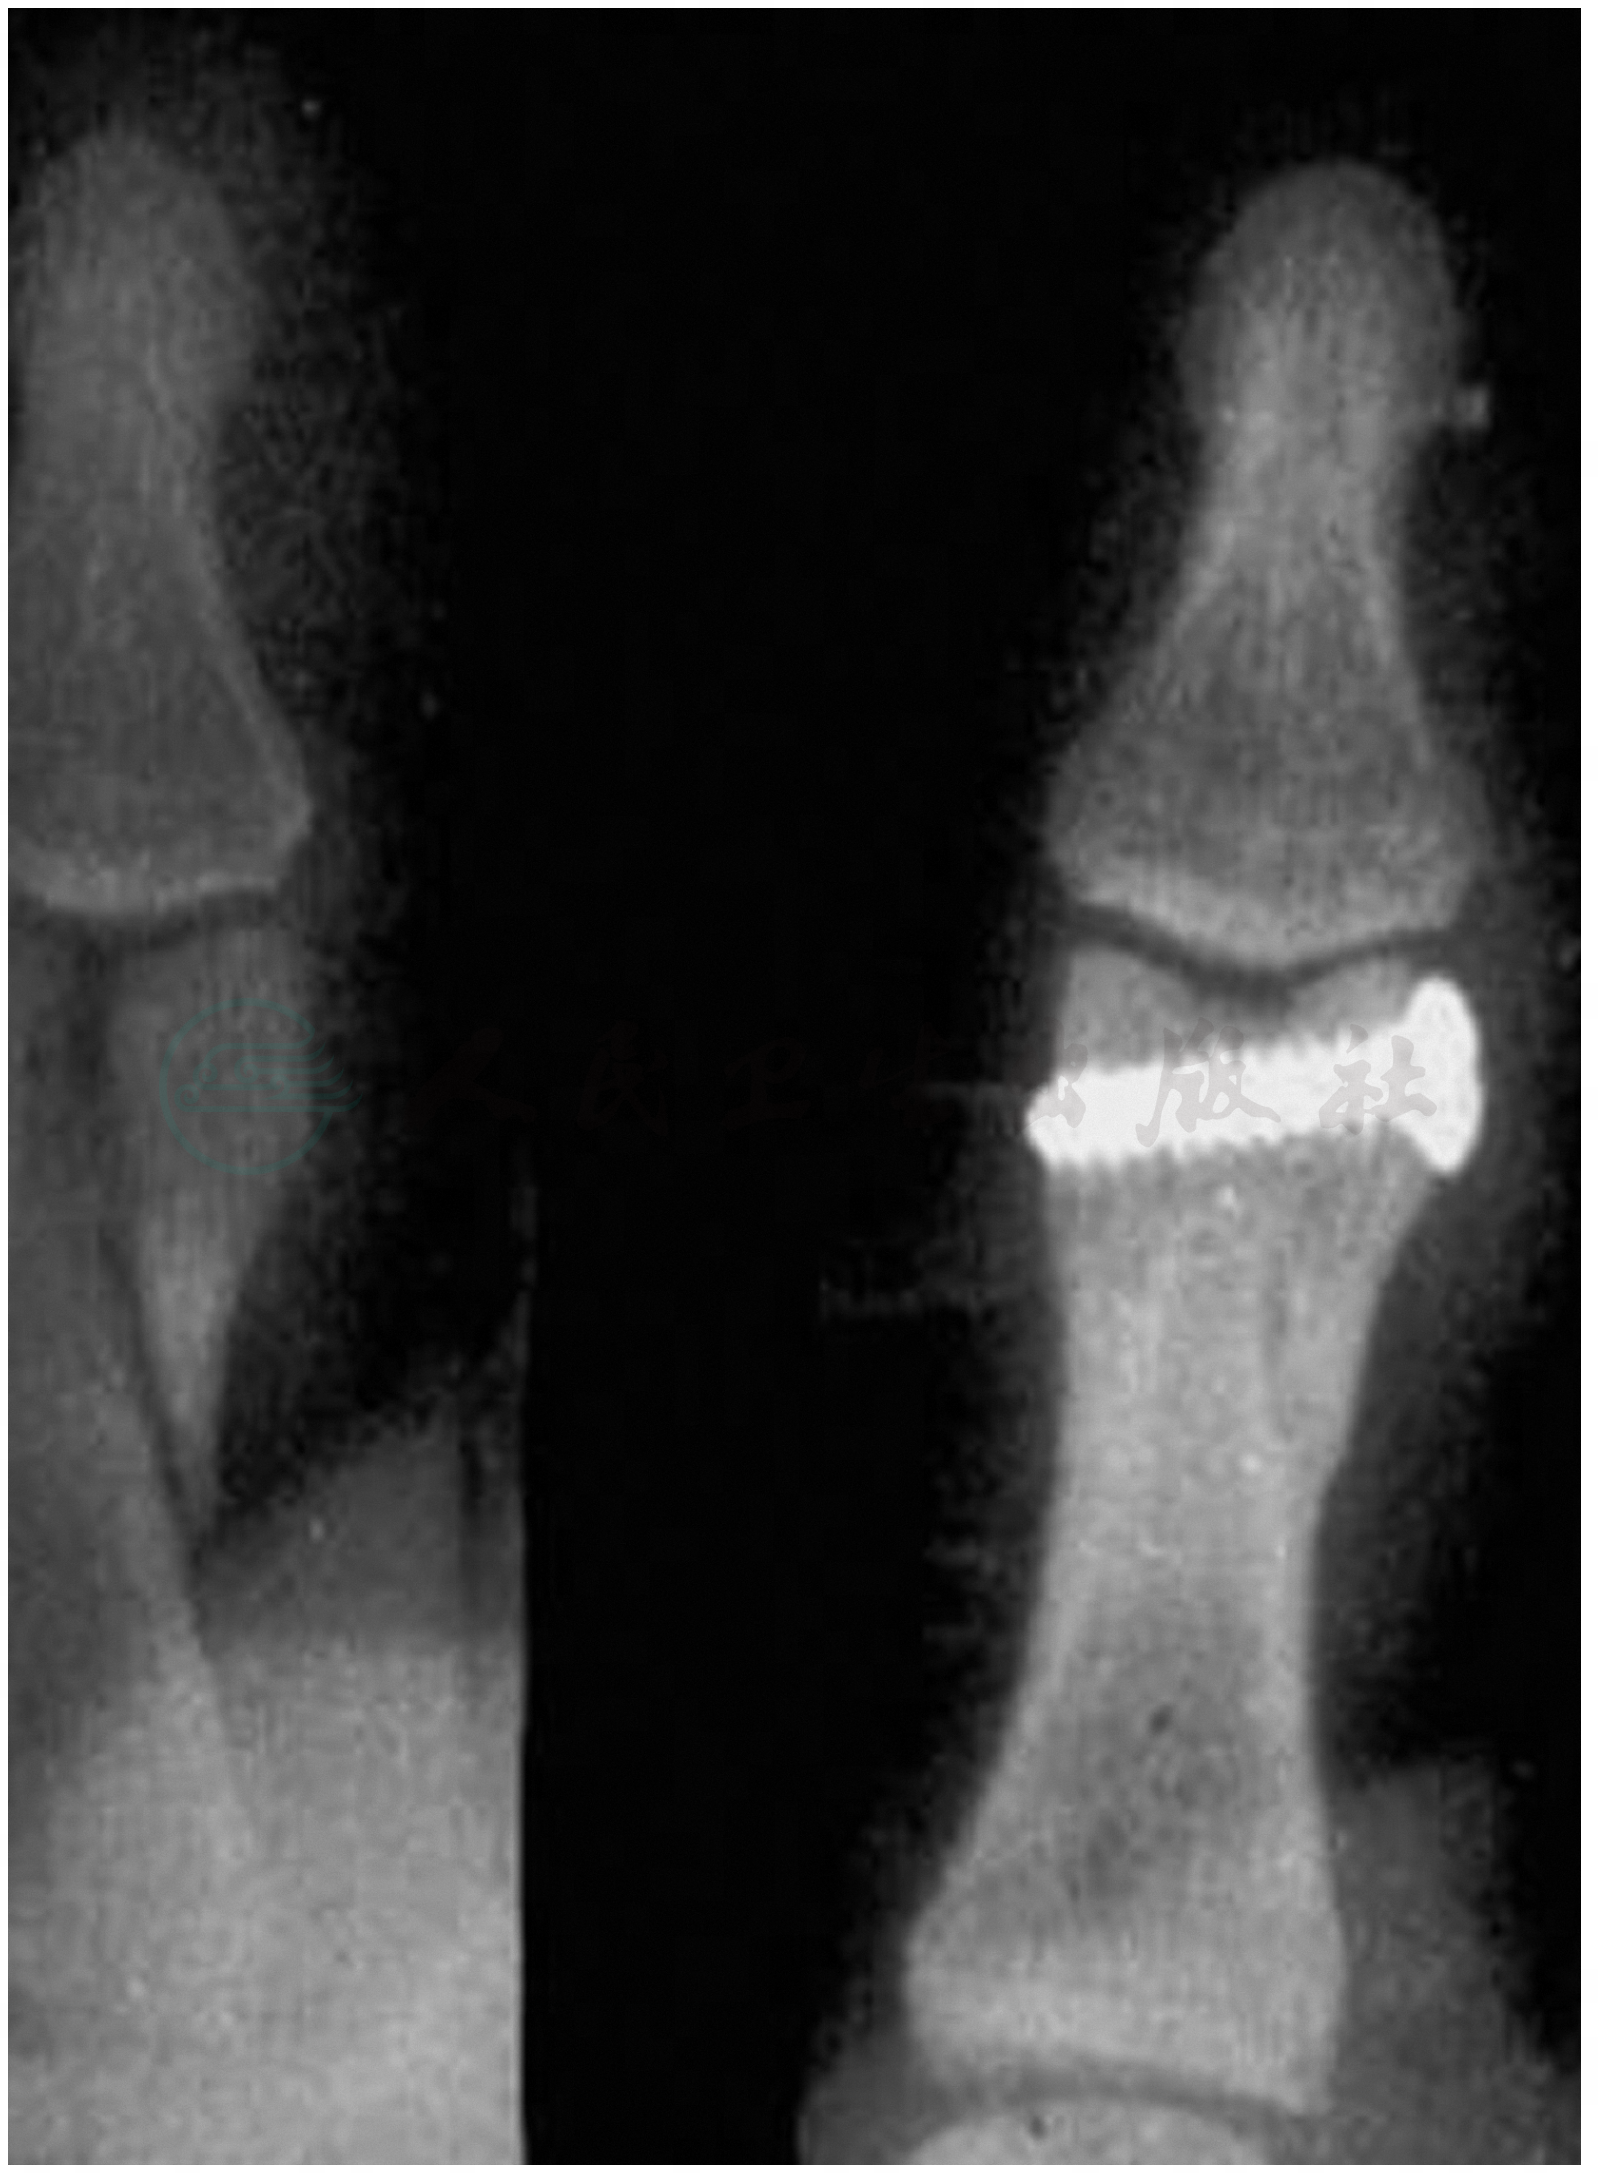

中节指骨骨折